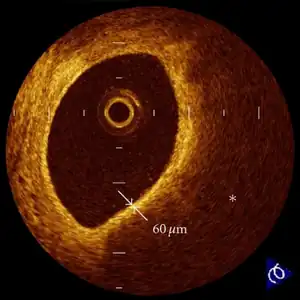

In those who have ACS, atheroma rupture is most commonly found 60% when compared to atheroma erosion (30%), thus causes the formation of thrombus which block the coronary arteries. Plaque rupture is responsible for 60% in ST elevated myocardial infarction (STEMI) while plaque erosion is responsible for 30% of the STEMI and vice versa for Non ST elevated myocardial infarction (NSTEMI). In plaque rupture, the content of the plaque are lipid rich, collagen poor, with abundant inflammation which is macrophage predominant, and covered with a thin fibrous cap. Meanwhile, in plaque erosion, the plaque is rich with extracellular matrix, proteoglycan, glycoaminoglycan, but without fibrous caps, no inflammatory cells, and no large lipid core. After the coronary arteries are unblocked, there is a risk of reperfusion injury due spreading inflammatory mediators throughout the body. Investigations is still underway on the role of Cyclophilin D in reducing the reperfusion injury.[11]

- ↑ Kubo, Takashi; Ino, Yasushi; Tanimoto, Takashi; Kitabata, Hironori; Tanaka, Atsushi; Akasaka, Takashi (2011). "Optical Coherence Tomography Imaging in Acute Coronary Syndromes". Cardiology Research and Practice. 2011: 312978. doi:10.4061/2011/312978. ISSN 2090-8016. Retrieved 10 November 2022.